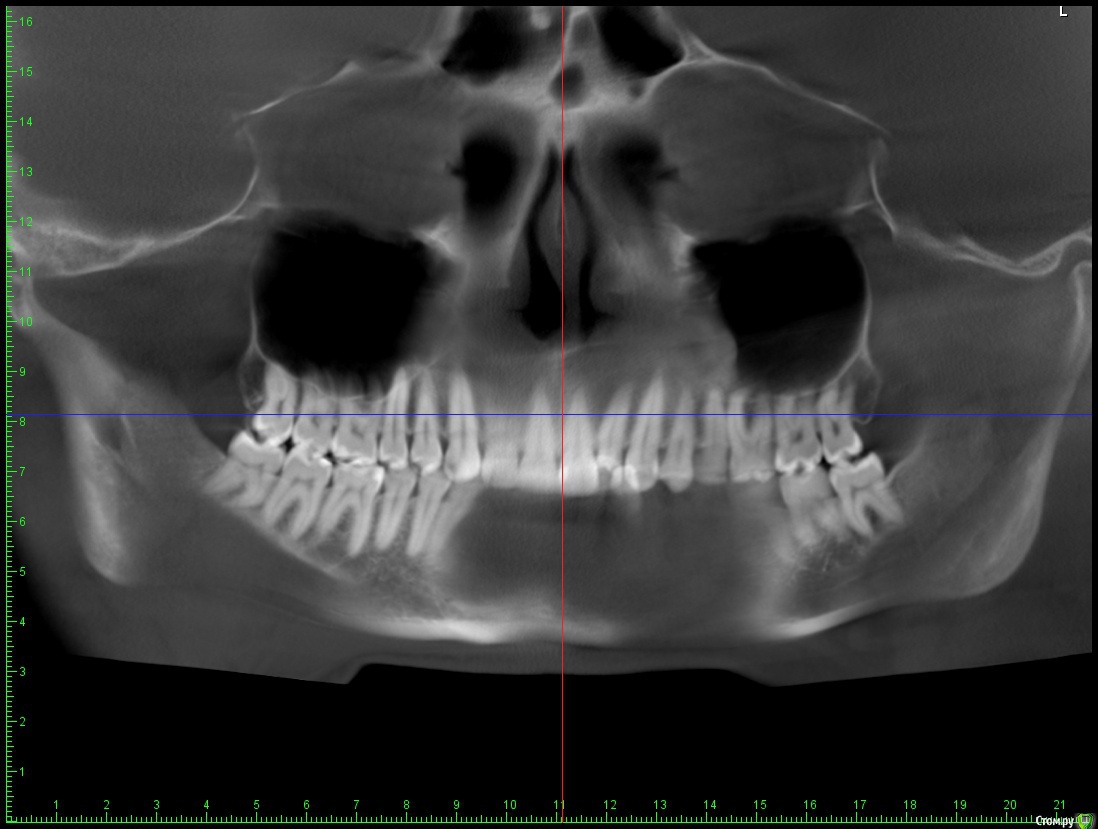

Беспокоит: Возраст 30 лет.  с 15 лет щелчки в суставе, полгода назад появилась периодическая боль - в области сустава, напряжение в жевательных мышцах, в шее  (с шеей вообще давние проблемы - не знаю, что первопричина болей), боли в затылке, голове. Глубокий прикус. Решил прикус исправлять в надежде, что боли уменьшатся.  На снимках видно, что челюсть нижняя заблокирована в заднем положении, мешают верхние резцы, головка сустава смещена

Часть из этого прикрепляю сюда. Ниже - заключение МРТ

Частичное переднее смещение суставного диска ВНЧС справа в положении с закрытым ртом, полная репозиция диска в положении с открытым ртом. Частичное переднее смещение наружного отдела суставного диска ВНЧС слева в положении с закрытым ртом (за счёт внутренней ротации диска), полная репозиция диска в положении с открытым ртом. Остеоартроз ВНЧС справа 1 ст.